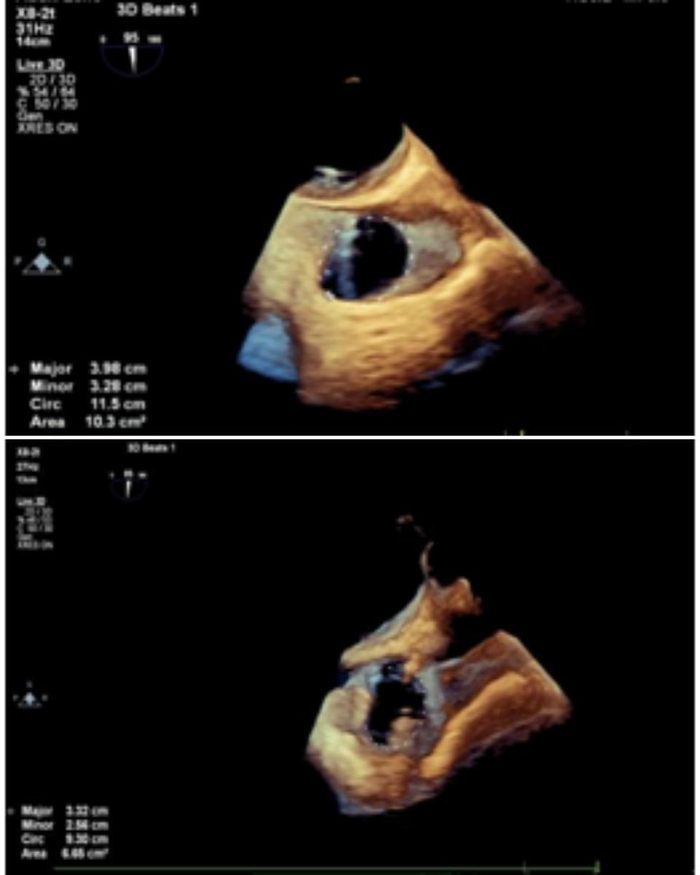

患者全麻后,行右侧颈静脉穿刺,将12T K-Clip®系统送达右心房内。在经食道超声引导下,对K-Clip®系统进行调姿,指向目标瓣环区,将K-Clip®锚定到位,打开夹持臂到最大角度,夹合,评估反流改善情况,解离器械退出系统。同样方法将14T K-Clip®系统夹合于前后瓣交界处。超声评估示反流下降至轻—中度,冠脉造影示冠脉血流与术前相同,达到满意效果,缝合血管,手术结束。患者术前重度三尖瓣反流。术前三尖瓣环面积10.3cm²,周长11.5cm;术后三尖瓣环面积6.6cm²,周长9.3cm。